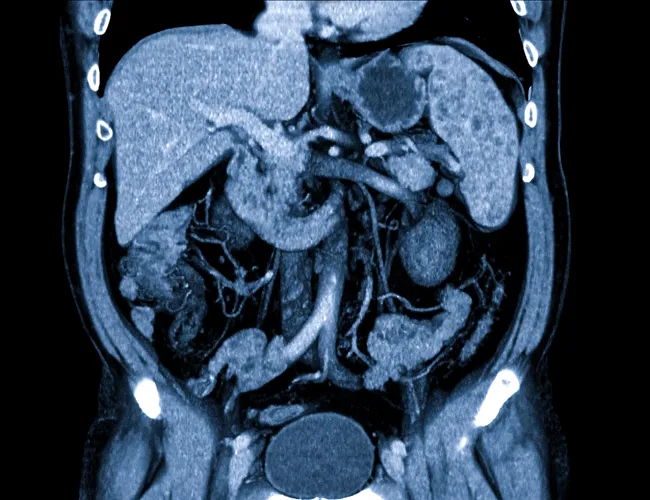

В последние годы мы наблюдаем настоящий прорыв в области искусственного интеллекта (ИИ), и его проникновение в медицину, в частности в гастроэнтерологию, открывает новые горизонты. Наш опыт показывает, что применение ИИ для анализа медицинских изображений, особенно МРТ, позволяет значительно повысить точность диагностики и эффективность лечения заболеваний желудочно-кишечного тракта. Эта статья – наш личный взгляд на то, как ИИ трансформирует гастроэнтерологию, основанный на опыте работы с этой технологией.

Искусственный интеллект в гастроэнтерологии – это использование алгоритмов машинного обучения и глубокого обучения для анализа медицинских данных, таких как изображения МРТ, КТ, эндоскопические снимки и результаты лабораторных исследований. Основная цель – помочь врачам в диагностике, прогнозировании и планировании лечения заболеваний ЖКТ.

ИИ активно применяется для диагностики и мониторинга различных заболеваний ЖКТ:

- Рак кишечника: ИИ может выявлять полипы и опухоли на ранних стадиях, что позволяет начать лечение своевременно.

- Воспалительные заболевания кишечника (ВЗК): ИИ может оценивать степень воспаления и прогнозировать течение заболевания.

- Болезни печени: ИИ может выявлять фиброз, цирроз и другие изменения в печени.

- Заболевания поджелудочной железы: ИИ может выявлять опухоли и воспалительные процессы в поджелудочной железе.